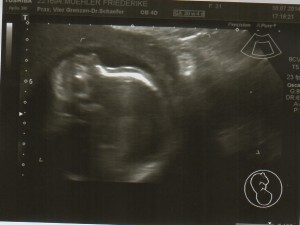

Heute gab es ein Fotoshooting der besonderen Art beim Opa auf Arbeit. Sein Kollege, der stellvertretende Chefarzt der Kinderklinik und gleichzeitig Guru des Ultraschalls, hatte sich bereit erklärt den werdenden Eltern noch ein paar aktuelle Fotos zu machen. Leider gab es kein 3D, aber dafür ein paar süße Fotos und vor allem Videos unseres Sohnemannes, der sich die ganze Zeit über ruhig verhielt und sich der Kamera, äh dem Schallkopf stellte.